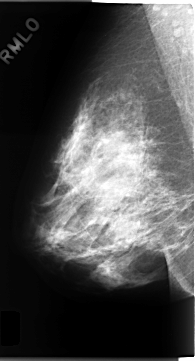

C_0150_1.RIGHT_MLO

RIGHT_CC LINES 4720 PIXELS_PER_LINE 2368 BITS_PER_PIXEL 12 RESOLUTION 50 NON_OVERLAY

RIGHT_MLO LINES 4688 PIXELS_PER_LINE 2528 BITS_PER_PIXEL 12 RESOLUTION 50 NON_OVERLAY